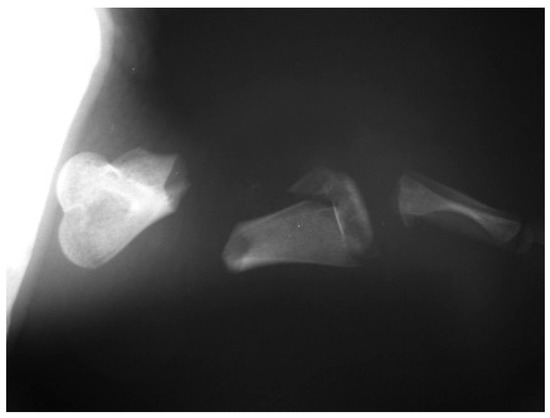

3.4. The Epiphyseal Fracture

The histological and micro-radiographic examination of the epiphyseal fracture (5th level) showed complete fracture healing. Slight differences in shape and in microscopic structures were observed between the fractured and the healthy control humerus: the compact bone appeared slightly thickened (+ 31%) whereas the spongiosa appeared rarefied (−30%). Additionally, the fractured epiphysis showed a different outline, probably due to a reaction to the stainless-steel pins (Figure 9a,b). No cartilage or fibrous tissue were observed at this level (Scheme 2).

Figure 9. Microradiographies examination of fractured (a) and healthy (b) epiphysis show complete fracture healing although slight differences in shape and microscopic structures.